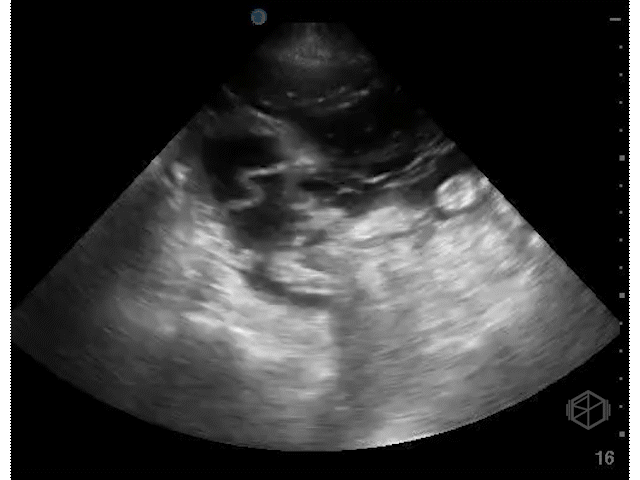

Several days later, she returned to the ED with hypotension, lightheadedness, and mild abdominal discomfort. Recognizing the potential urgency, Dr. Weinberger immediately performed a POCUS, which revealed the following:

The patient had complex free fluid in the abdomen, noted with septations and fibrinous stranding. Surgery was immediately notified and a CT was performed a little while later that showed a moderate amount of free air in the abdomen, fluid suspicious for peritonitis, and concern for a leak at the small bowel connection in the right lower quadrant. In surgery, cloudy bile-tinged fluid was found but no stool. The previous connection had poor blood flow and a small leak. That section was removed, a new connection was made between healthy bowel, and the abdomen was closed. The patient tolerated the procedure and did well.